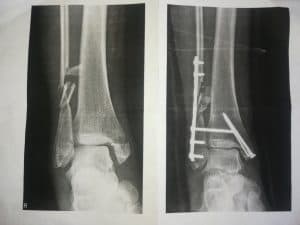

In de figuur 3 zien jullie 2 uitgeprinte röntgenfoto’s. De linker opname is gemaakt vóór de operatie en de rechteropname na de operatie. Beide foto’s laten de voorzijde van mijn rechter enkel zien.

Mijn binnenste enkelknokkeltje (rechts op de foto – uiteinde van mijn scheenbeen) is met een schroef weer vastgezet aan mijn scheenbeen. Met een plaat en schroeven heeft de chirurg mijn kuitbeen proberen te repareren. En verder is er nog een lange horizontale schroef geplaatst om mijn kuitbeen aan mijn scheenbeen te fixeren. Dit is ter ondersteuning van het herstel van de zogenaamde syndesmose. Een syndesmose is een verbinding van beenderen door sterk bandweefsel (ligamenten). Deze banden maken dat er een sterke vork ontstaat waar de voet in opgesloten wordt en in kan scharnieren. Deze banden zijn niet in beeld te brengen op een röntgenfoto. Toch weten we dat de syndesmose beschadigd is omdat mijn voet zich tijdens de val heeft kunnen verplaatsen naar de buitenzijde van mijn onderbeen (zie figuur 2 en 3 in mijn verhaal van 28 december).